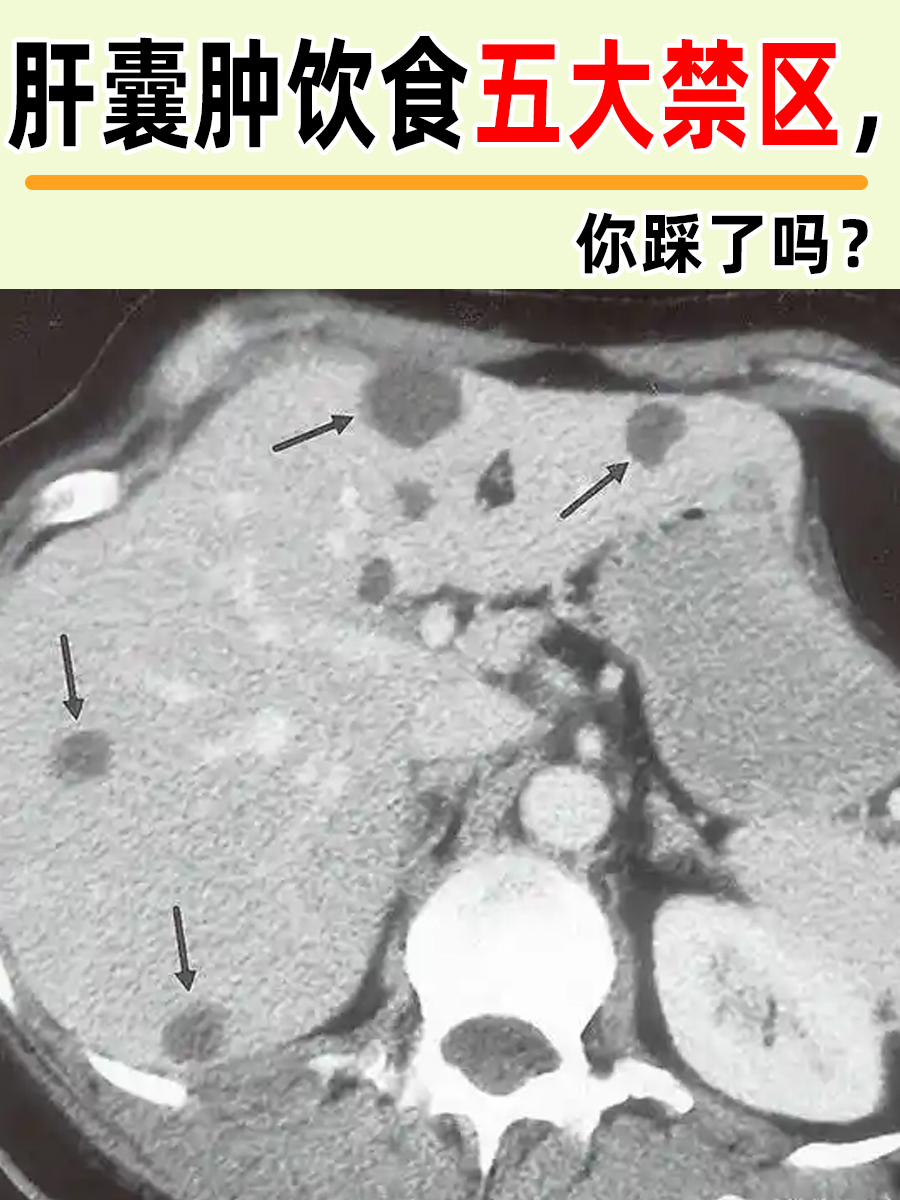

👉肝囊肿,作为肝脏的一种良性病变,虽然大多数情况下不会引发严重症状,但仍需患者在日常生活中予以关注,尤其是饮食方面。合理的饮食习惯不仅能够减轻肝脏负担,还能有效防止肝囊肿的进一步发展和恶化。

📍肝囊肿患者在饮食上需特别注意以下五大禁忌: